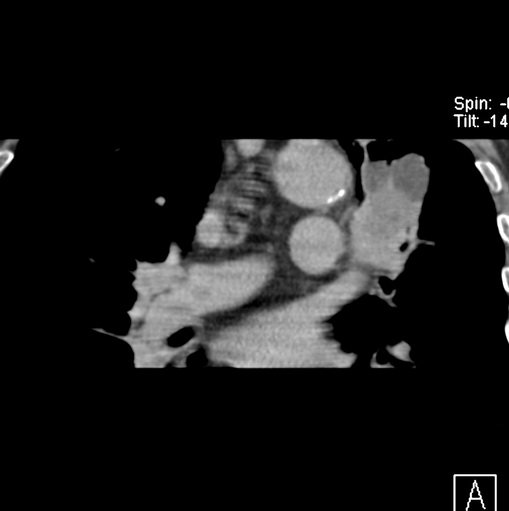

男性患者 81岁 咳嗽 咳痰 咯血

肿块贴近左肺门,包绕左上肺动脉,形态不规则。肿块增强扫描中度强化。纵膈内主动脉弓左旁间隙、气管隆突前、下间隙见多枚淋巴结影。综上考虑左侧中央型肺癌可能性大。图片没有完整上传,尤其是左肺上叶支气管分支层面没有上传,因此不好判断是叶支气管中断还是段支气管中断。另外,下图红色部分所示是“黏液支气管征”吗?